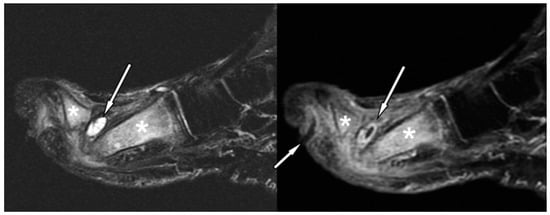

- Sinus tract and abscess: Sinus tracts and abscesses are some of the major findings in osteomyelitis. Morrison et al. determined the usefulness of primary and secondary MRI signs of OM and found that the identification of a sinus tract showed high specificity (average, 85%) for the diagnosis of osteomyelitis in the adjacent bone [47]. Sinus tracts typically extend from skin ulcers to tendon sheaths, bones, or joints, and they represent a route for the subsequent spread of infection leading to abscesses, septic tenosynovitis, and/or osteomyelitis [47]. Sinus tracts appear as linear fluid signal intensity on fluid-sensitive fat-suppressed images and display a characteristic “tram-track” pattern of the enhancement on contrast-enhanced images. The latter are the most sensitive MRI feature for detecting sinus tracts (Figure 3). Abscess is seen as a focal fluid collection that is hypointense on T1-weighted images and hyperintense on fluid-sensitive fat-suppressed images, with a thick rim post-contrast enhancement, due to the presence of granulation tissue (Figure 3). The presence of rim enhancement is essential in distinguishing abscesses from cellulitis or phlegmons, which present diffuse post-contrast enhancement [42,43,46].